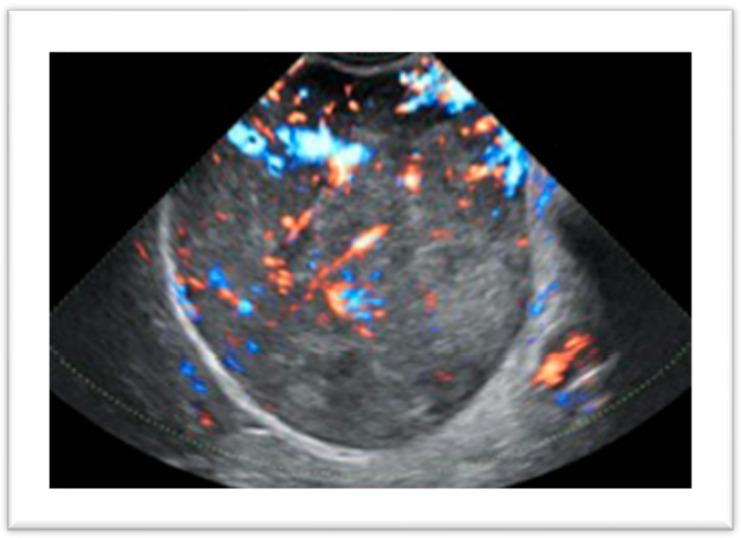

Uterine leiomyomas are the most common benign uterine tumors in women and are often asymptomatic, with clinical manifestation occurring in 20-25% of cases. The diagnostic pathway begins with clinical suspicion and includes an ultrasound examination, diagnostic hysteroscopy, and, when deemed necessary, magnetic resonance imaging. The decision-making process should consider the impairment of quality of life due to symptoms, reproductive desire, suspicion of malignancy, and, of course, the woman's preferences. Despite the absence of a definitive cure, the management of fibroid-related symptoms can benefit from various medical therapies, ranging from symptomatic treatments to the latest hormonal drugs aimed at reducing the clinical impact of fibroids on women's well-being. When medical therapy is not a definitive solution for a patient, it can be used as a bridge to prepare the patient for surgery. Surgical approaches continue to play a crucial role in the treatment of fibroids, as the gynecologist has the opportunity to choose from various surgical options and tailor the intervention to the patient's needs. This review aims to summarize the clinical pathway necessary for the diagnostic assessment of a patient with uterine fibromatosis, presenting all available treatment options to address the needs of different types of women.

子宫平滑肌瘤是女性最常见的良性子宫肿瘤,通常无症状,仅20% - 25%的病例会出现临床表现。诊断流程始于临床怀疑,包括超声检查、诊断性宫腔镜检查,必要时还包括磁共振成像。决策过程应考虑症状对生活质量的损害、生育意愿、恶性肿瘤怀疑,当然还有患者的偏好。尽管尚无根治方法,但子宫肌瘤相关症状的管理可受益于各种医学疗法,从对症治疗到旨在减轻肌瘤对女性健康临床影响的最新激素药物。当医学治疗对患者并非最终解决方案时,它可作为桥梁为手术做准备。手术方法在肌瘤治疗中仍起着关键作用,因为妇科医生有机会从各种手术选择中进行挑选,并根据患者需求调整干预措施。本综述旨在总结子宫纤维瘤病患者诊断评估所需的临床路径,呈现所有可用治疗方案以满足不同类型女性的需求。